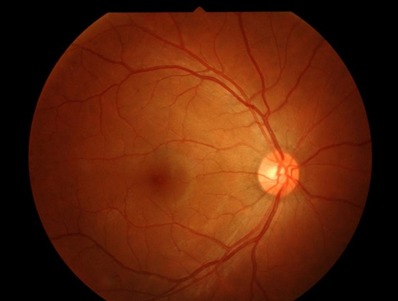

🔬 Comprehensive Retina Evaluation

Detailed retinal examination by experienced ophthalmologist

Fundus photography for documentation and monitoring

Early detection of silent retinal diseases

👁️ Diabetic Retinopathy Management

Screening and grading of diabetic eye disease

🧾 Key Retina Conditions Treated

Diabetic Retinopathy

Retinal Detachment

Macular Degeneration

Retinal Vein Occlusion

Macular Hole

Epiretinal Membrane

Vitreous Hemorrhage